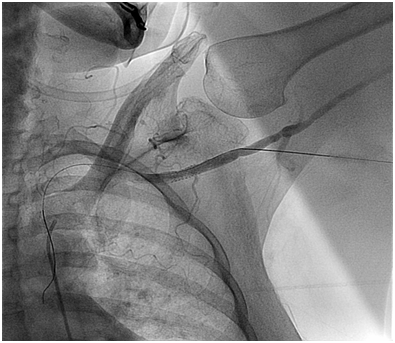

Figure 2 Coronal section showing origin of innominate artery > 2 L CCA diameter from top of arch in type III aortic arch in one of our TAVR patients.

One clinical implication of the ubiquitous nature of Type III arches in our very elderly aortic stenosis patients relates to percutaneous access for interventions such as TAVR. In specific, with the left arm hyper extended over the head, the trajectory of the left axillary and left subclavian arteries falls along the trajectory of a Type III arch (Figure 3). This trajectory makes an axillary approach an attractive alternative to trans: apical and trans: aortic approaches in patients with advanced lung disease or severe peripheral artery disease (PAD) who are not good candidates for either transfemoral or transapical/transaortic approaches. Finally, this information coupled with the fact that axillary artery size is quite comparable to femoral artery size in most patients,8,9 a totally percutaneous left axillary artery approach utilizing a double Per close large bore arteriotomy closure at the end of procedure is highly feasible for a totally percutaneous TAVR as demonstrated by Shäfer et al.10 and also for totally percutaneous Impella device insertion and removal (Figures 4A to 4E) as shown by our group.8

Figure 3 3D rendering of aortic arch and origin of great vessels in the same patient.